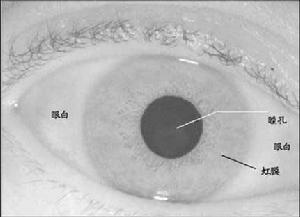

正常人的房角1、發作時常有情緒紊亂、過勞,長時間閱讀等誘因有虹視及霧視、眼脹,休息睡眠後可自行緩解。

虹膜1、急性閉角型青光眼病程遷延或亞臨床期的反覆發作造成的周邊虹膜前粘連周邊虹膜前粘連。